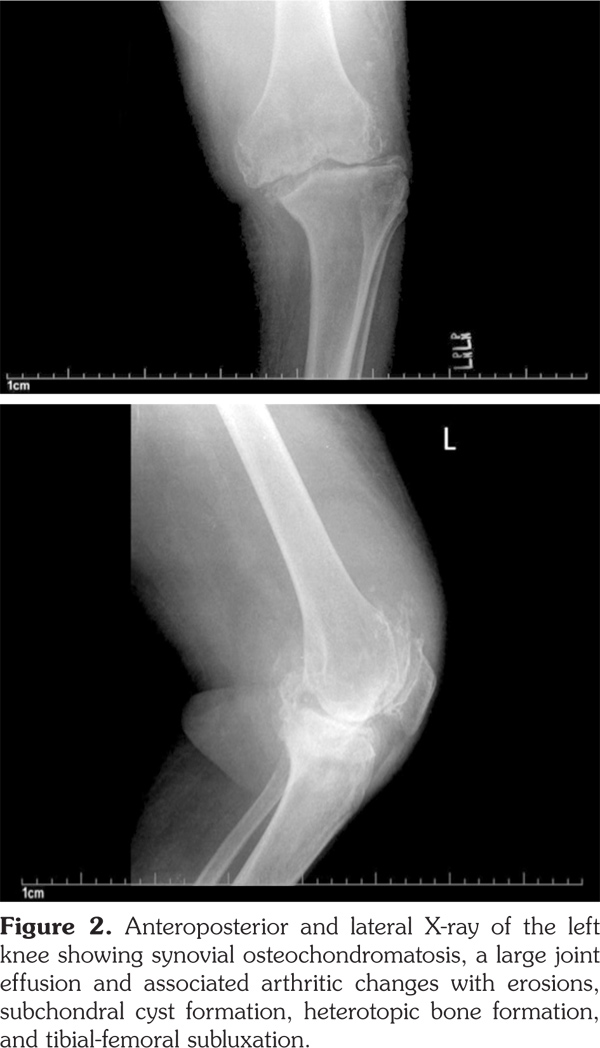

Plain radiographs of the knee joints revealed joint effusions with multiple rounded intra-articular loose bodies, erosions on the medial aspect of the tibial plateau, tricompartmental joint space narrowing, osteophytes, subchondral cyst formation, heterotopic bone formation, and lateral subluxation of the tibia on the femur (Figure 1, 2).